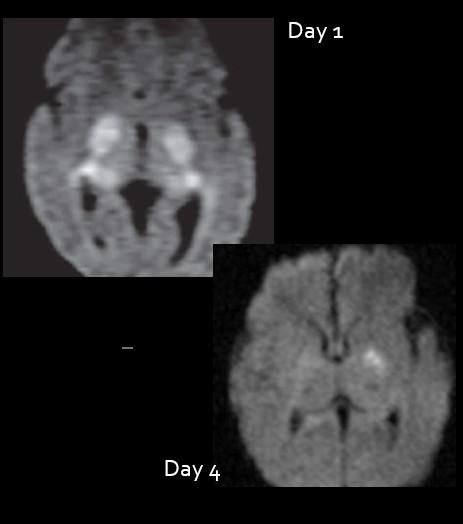

Pre Lecture Test: Abnl DWI in a neonate with Seizures.

Choices: HIE….Infection (specific?)….Metabolic… other

Image

Too Early or

Too Late!

Initial exam optimum at 72-84 hours (Follow up MR imaging at day 7-10 if discordant with clinical exam)

2 days

4 days Image too soon…underestimate injury. Image too late…miss injury.

Day 4 (72 hours)

Pseudonormalization

Day 7